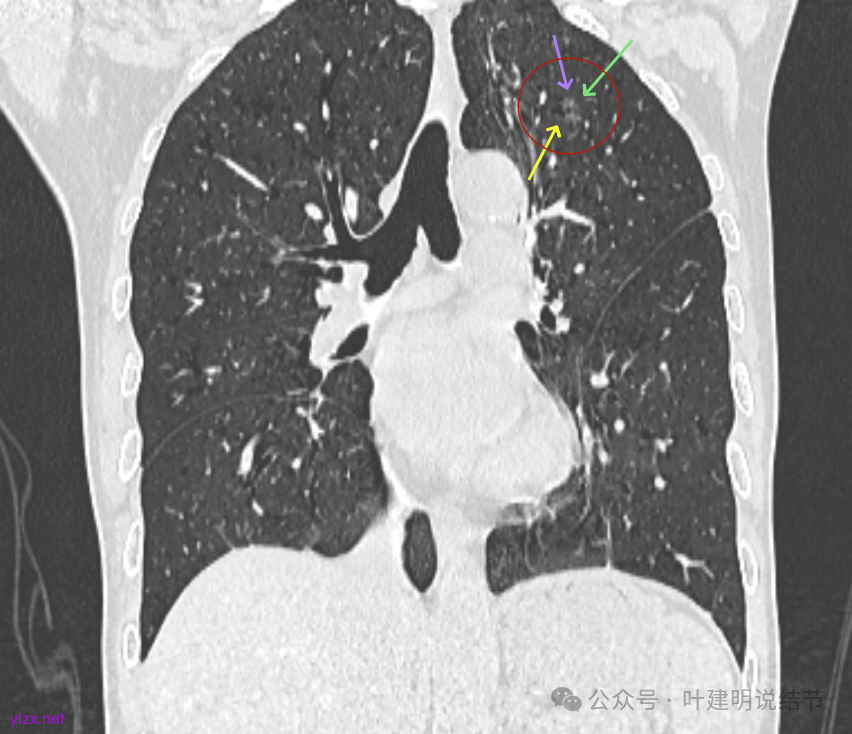

再看2024年9月复查的:

右上的仍小而淡,轮廓仍是清楚的。

左上的病灶略显模糊,密度不太纯,较前相仿。

右上的较前略增大,且有空泡征较豙明显些,肿瘤的成分仍是纯磨密度。

左上病灶也是较为纯的,边缘不光滑,大小似乎略大一点点,不太显著。

右上冠状位显示病灶纯磨,血管进入穿行,灶内空泡征,表面毛刺征,没有明显实性成分。

左上病灶冠状位显示纯磨,部分连续细毛刺,灶内有扩张的细支气管似的,整体轮廓清。